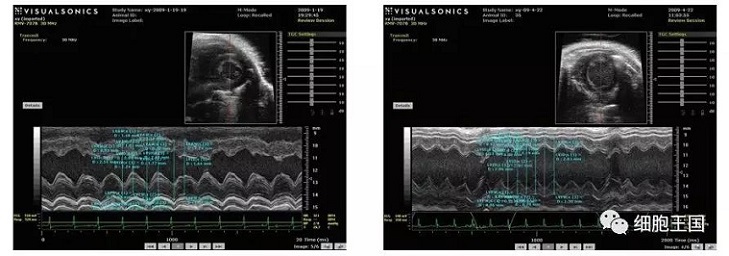

干細(xì)胞移植后各臟器呈現(xiàn)較之前狀態(tài),具體表現(xiàn)在以下幾個(gè)方面(如圖)。

超聲心動(dòng)圖顯示對(duì)照組左室舒張期容積低于移植組